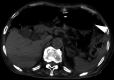

Emphysematous gastritis and gastric emphysema are different diseases. Sometimes, we treat the diseases without distinguishing them clearly because both are rare, and the mortality rate of emphysematous gastritis cases is high (55%). Gastric emphysema is more well known than is emphysematous gastritis after percutaneous endoscopic gastrostomy (PEG) placement (80%). Particularly, it is a self-healing disease, and treatment with antibiotics is not required. CT is commonly used to diagnose emphysematous gastritis and gastric emphysema. The amount of radiation exposure is a concern for performing multiple CTs following air disappearance in the gastric wall. Here, we report the case of a 92-year-old man with gastric emphysema after PEG. It was useful to follow-up the patient by performing radiographic examination, and the disease was managed conservatively without antibiotic administration. We report that distinguishing gastric emphysema from emphysematous gastritis was necessary. Moreover, performance excessive tests and treatments should be avoided.